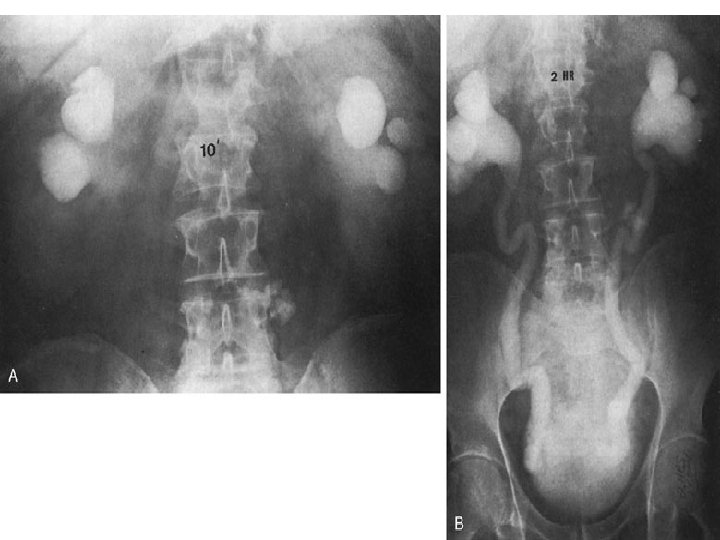

IVP Prostatik indentasyon - Balık oltası görünümü - Mesane taşı - Trabekülasyon artışı, sellüler ve divertiküller - Post- voiding grafide rezidüel idrar saptanması